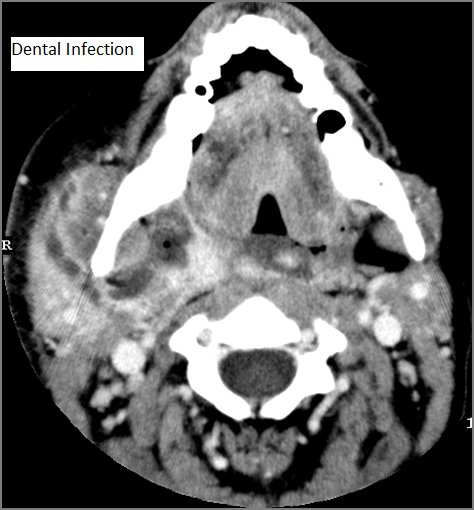

Oral Cavity, Floor of the Mouth, Maxilla and Mandible

There is significant abnormality of these structures that would be an alternate explanation for the patient’s symptoms. [Yes/No]